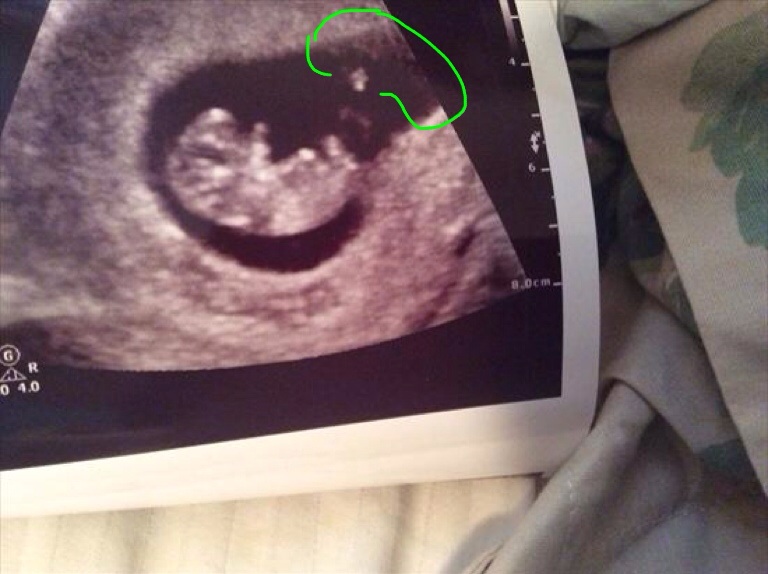

Attachment 18961

If it's an abdominal U/S I'll say girl because gestational sac is pretty much where mine was and I'm having a girl. If internal then it's a boy.

The nub looks very girlie. x

Both of these were abdominal. :)